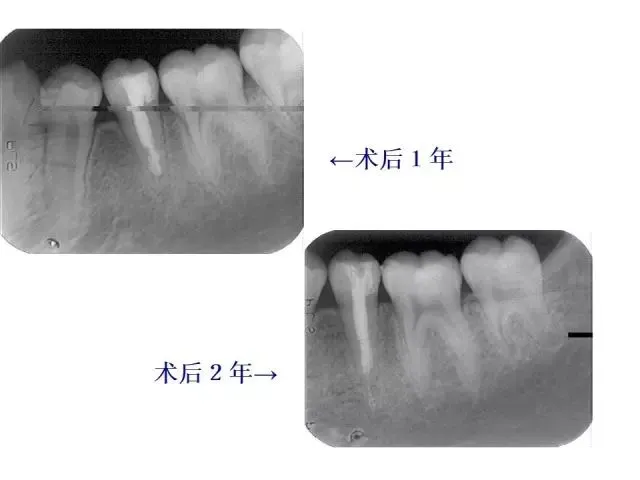

>PPT典藏 | 根尖诱导成型术

PPT典藏 | 根尖诱导成型术